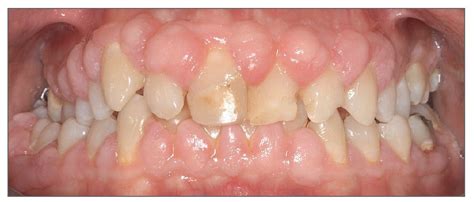

Aumento Gingival Inducido por Placa/Fármacos

En esta condición el problema radica en que los tejidos gingivales son hiperplásicos y cubren las coronas clínicas, lo que da lugar a un aspecto poco estético. La mayoría de las veces esta condición está relacionada con la presencia de placa dental y de inflamación pero también puede verse asociada a medicaciones como la fenitoína, la ciclosporina y bloqueantes de los canales del calcio. El tratamiento de estos casos debe enfocarse hacia la higiene oral meticulosa. A veces es necesario recurrir a cirugía periodontal para eliminar la excesiva cantidad de tejidos blandos.